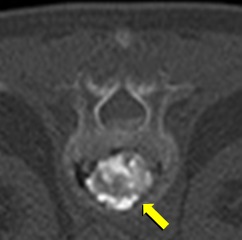

[非血管系IVR] 圧迫骨折(胸椎) 手術:経皮的椎体形成術(PVP)

CT画像

MRI画像